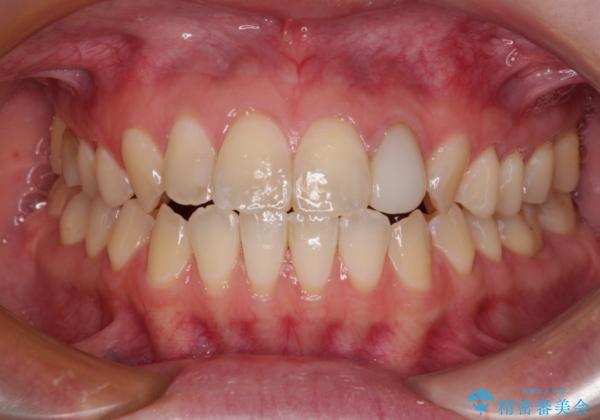

開咬を治す インビザラインによる矯正治療

- 上下前歯の開咬を気にして来院された患者様です。

開咬はインビザラインを用いると有意に改善ができるため、インビザラインによる矯正治療を行うこととしました。

途中1年8ヶ月ほど来院されず、久しぶりの来院後は治療が面倒とのことで、前歯の叢生や隙間に不十分な点が残った状態での終了となりました。